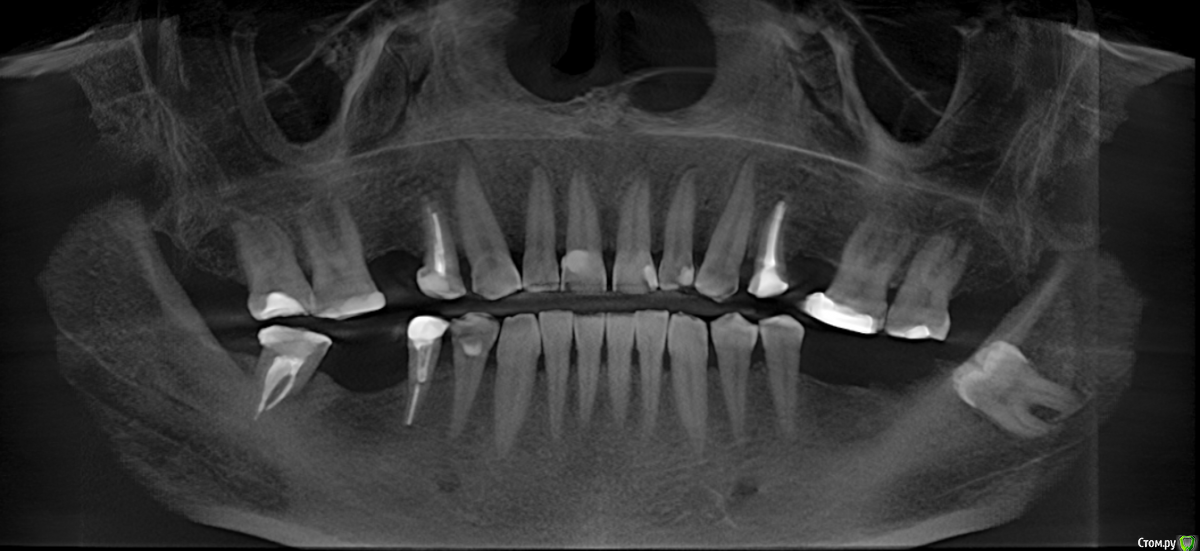

se77777 Опубликовано 5 декабря, 2019 Поделиться Опубликовано 5 декабря, 2019 (изменено) Добрый день, есть рекомендации: Первый этап: Удаление 26, 27 Импланты 36, 26,2537 был удален 17.11.2019 Второй этап: Удаление 15 (там на КТ обнаружилась гранулема)Импланты 15,16,46 Пациенту 52 года.Есть другие варианты?Целесообразно ли установить при удалении имплант 27 из расчета в будущем сделать имплант на 37?Есть ли осложнения (недостаток костной ткани и т.п.)? С уважением,Сергей. Изменено 5 декабря, 2019 пользователем se77777 Ссылка на комментарий

red_butler Опубликовано 5 декабря, 2019 Поделиться Опубликовано 5 декабря, 2019 Ваш снимок является панорамной реконструкцией, ответить на все вопросы нему не получится. 2.6 2.7 хотят удалять из за того что они опустились? Ортодонтическую подготовку обсуждали?Место по высоте есть, ширину нужно смотреть на срезах Кт.Финансовые вопросы на форуме не обсуждаются 1 Ссылка на комментарий

se77777 Опубликовано 6 декабря, 2019 Автор Поделиться Опубликовано 6 декабря, 2019 (изменено) 26 и 27 опустились, места по высоте не нашли.КТ есть.https://yadi.sk/d/fcS6721v155x_Q Изменено 6 декабря, 2019 пользователем se77777 Ссылка на комментарий